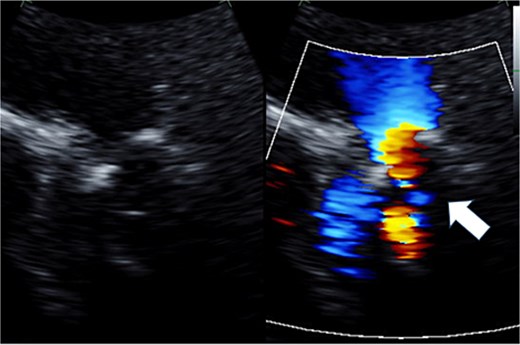

Preoperative transthoracic echocardiography: moderate pulmonary regurgitation. The regurgitant jet is indicated by the white arrow.